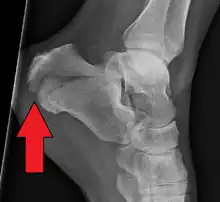

A calcaneal fracture is a break of the calcaneus (heel bone).[1] Symptoms may include pain, bruising, trouble walking, and deformity of the heel.[1] It may be associated with breaks of the hip or back.[1]

It usually occurs when a person lands on their feet following a fall from a height or during a motor vehicle collision.[2][1] Diagnosis is suspected based on symptoms and confirmed by X-rays or CT scanning.[1]